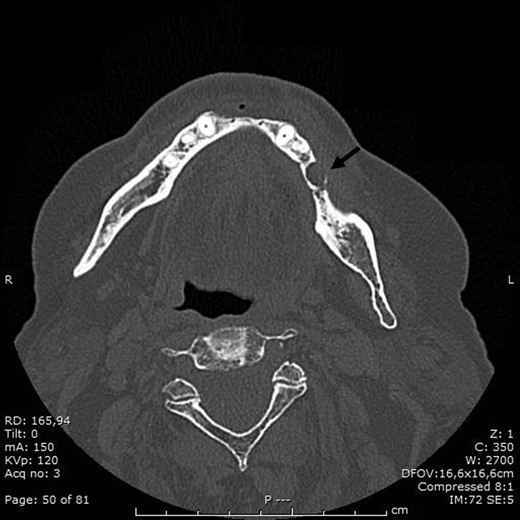

BRONJ had been clinically diagnosed at the patient’s first visit and confirmed radiologically by the dental x-ray and CT performed in September 2016, which showed marked demineralization of the anterior portion of the orbital ethmoid wall on the right, left mandibular osteonecrosis in the premolar region, a small periapical granuloma in position 44 and diffuse upper and lower alveolar atrophy.

In November 2016 the patient underwent surgery under general anaesthesia (same technique used for the first patient described) (Fig. 4A–D). The mesial and distal bone curettage margins were dictated by the x-ray images (Fig. 5) which identified above all the radio-opaque areas, often associated with a periosteal reaction, as well as by the need to remove any bone sequestra present. The HAM was 3 × 3 cm2 in size and was positioned over the curetted area and under the mucosal flap.